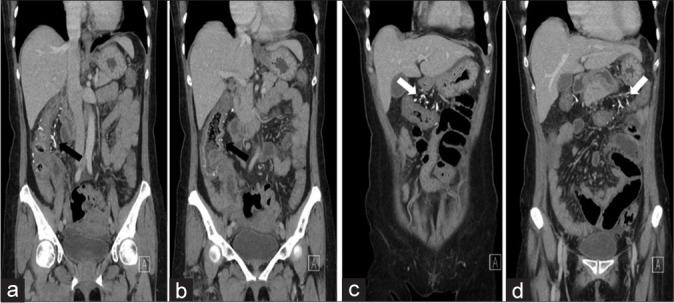

Phlebosclerotic Colitis is a rare, potentially life-threatening condition of unclear etio-pathogenesis seen almost exclusively in Asians and people of Asian descent. The condition predominantly affects the right hemicolon and imaging plays a crucial role in its diagnosis. Here we report the only second documented case of phlebosclerotic colitis in North America in a 60-year-old Canadian resident of Vietnamese descent with a history of consuming herbal medication () in soup for 2-3 decades.

静脉硬化性结肠炎是一种罕见的、可能危及生命的疾病,其病因和发病机制尚不清楚,几乎仅见于亚洲人和亚裔人群。该病主要影响右半结肠,影像学检查在其诊断中起着关键作用。在此,我们报告北美第二例有记录的静脉硬化性结肠炎病例,患者为一名60岁的加拿大越南裔居民,有2至3十年在汤中食用草药的病史。